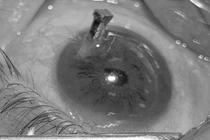

Tình trạng mắt trái của anh T.V.T sau khi được phẫu thuật/ Ảnh Bệnh viện Trung ương Thái Nguyên

Người bệnh là anh T.V.T (32 tuổi, trú tại phường Lương Sơn, tỉnh Thái Nguyên) nhập viện trong tình trạng rách góc mắt trong, đứt lệ quản trên, rách da mi phức tạp và dập nát tổ chức mi, bao gồm cả phần sụn mi - một tổn thương nặng, nguy cơ ảnh hưởng nghiêm trọng đến chức năng thị giác và thẩm mỹ vùng mắt.

Ngay sau khi tiếp nhận, các bác sĩ đã khẩn trương tiến hành phẫu thuật nối lệ quản, phục hồi góc mắt và tái tạo tổ chức mi. Với sự tỉ mỉ trong từng thao tác, sau gần 2 giờ phẫu thuật, ê-kíp đã bảo tồn được thị lực, chức năng nâng mi và phục hồi hình thái thẩm mỹ vùng mắt cho người bệnh.